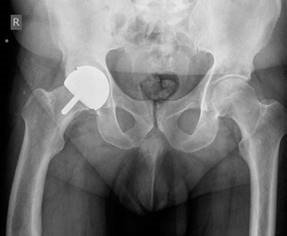

Hip structured oral questions Structured Hip oral examination question 1 EXAMINER : This is a radiograph of a…